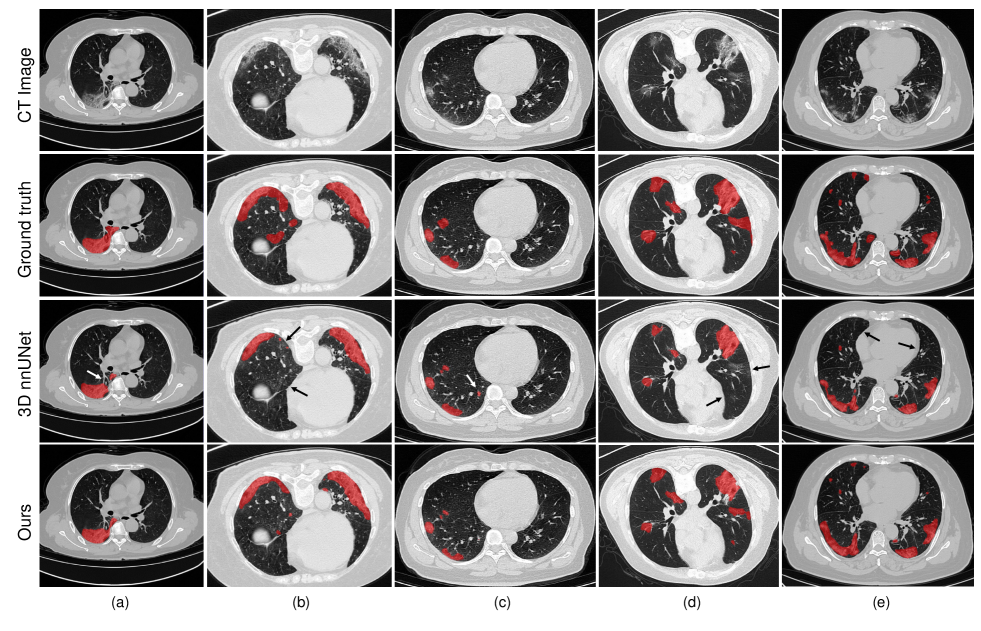

Refer to caption

Figure 4: Visual comparison of COVID-19 infection segmentation by different methods on 2D COVID-SemiSeg dataset. As can be observed, our method can generate segmentation results with more accurate boundaries and less segmentation mistakes in small infection areas, which is closer to the ground truth.

In this subsection, we compare our method with state-of-the-art methods for 2D medical image segmentation, including U-Net [37], U-Net++ [50], Dense-UNet [49], Attention-UNet [47], Gated-UNet [48], Inf-Net and Semi-Inf-Net [30]. Quantitative results are shown in Table V. As can be observed, our proposed method outperforms all comparing methods on all evaluation metrics by a large margin, validating the effectiveness of our framework. Paired T-test shows that the improvements are statistically significant at p<0.05𝑝0.05p<0.05. Besides, we visualize some segmentation results of our method in Fig.4. These results indicate that our segmentation results are closer to the ground truth with less mis-segmented areas and outperform other methods significantly. For semi-supervised setting, we additionally integrate unlabeled COVID-19 cases of COVID-SemiSeg Dataset into the relation-driven training in our framework. These unlabeled cases can be utilized for the regularization of feature relation to achieve more consistent and robust learning and further improve the segmentation performance slightly.